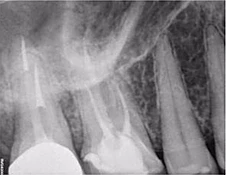

Một phụ nữ 54 tuổi với tiền sử chấn thương tới phòng khám với lý do răng 41 đau và áp xe gây khó khăn khi ăn nhai. Trên XQ 2 chiều thấy tổn thương tiêu ở răng 41 và áp xe ở răng 42 (Hình 1 và 2), rất khó để biết phạm vi nội tiêu theo hướng ngoài – trong. Tổn thương trông có vẻ rộng, nhưng có phá ra phía ngoài hay trong không? May mắn thay, phim chụp từ máy CS 8100 cho thấy nội tiêu chỉ nằm trong phạm vi ống tủy (hình 3 – 5), do đó tôi tự tin rằng điều trị tủy có thể giải quyết vấn đề của bệnh nhân, hai răng này sau đó được đặt Ca(OH)2 rồi trám bít (hình 6 và 7)

Bệnh nhân nữ 68 tuổi chuyển tới phòng khám của tôi sau khi bác sĩ tổng quát thấy tổn thương “nghi ngờ” nhưng không xác định được. Bệnh nhân không có triệu chứng và cũng không rõ vì sao mình được chuyển tới đây. Sau khi khám lâm sàng, tôi nghi ngờ có tổn thương ngoại tiêu. Tuy nhiên, bệnh nhân vẫn còn nghi ngờ về phim 2 chiều (Hình 8), thông tin trên phim chưa đáng để lo lắng, do đó cô ngần ngại chấp nhận điều trị.

Hình 8: XQ trước điều trị

Tuy nhiên, phim 3D cho thấy rõ ràng có tổn thương ngoại tiêu (Hình 9 và 10). Trên phim cũng đồng thời cho thấy tổn thương là ngoại tiêu cổ răng xâm nhập ở mặt trong. Trong buổi hẹn tư vấn, tôi đã cho bệnh nhân quan sát rõ tổn thương và đưa ra đề xuất điều trị.